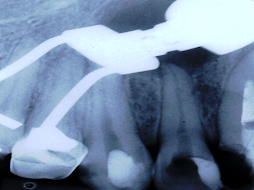

ENDO-OCLUSÃO

A ENDODONTIA PODE FRACASSAR SE A OCLUSÃO TIVER AJUSTADA

PELO DESGASTE APRESENTADO DA PARA IMAGINAR O QUE VAI ACONTECER!!!

SERÁ?

DOR!!!!!!!!!!!!!!!!!

É DA ENDO?

TINHA QUE DAR NISTO!!!!

E AGORA?